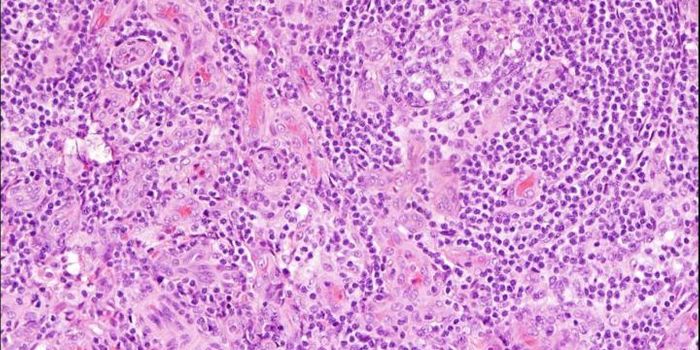

FEB 09, 2024CancerHistopathology describes the process of examining pieces of tissue using a microscope. Light microscopic (LM) exam ...